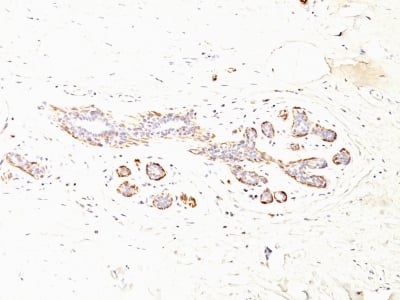

(Formalin-fixed, paraffin-embedded human Breast Carcinoma stained with SM-MHC Monoclonal Antibody (MYH11/923 + SMMS-1).)

IHC (Immunohiostchemistry)